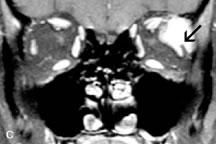

PATIENT PREPARATION Before MRI is performed, patients must be screened and prepared to avoid the potential hazards associated with the strong magnetic field. Patients who have ferrous aneurysm clips or cardiac pacemakers, who depend on life-support equipment, or who retain a possible metallic intraocular foreign body are not candidates for this imaging modality. MRI cannot be performed on obese patients who cannot fit into the bore of the magnet. Patients who are claustrophobic may not tolerate a prolonged period of study within the confines of the magnet, whereas others might do well if given a mild sedative. All worn metallic objects (e.g., necklaces, watches) should be taken off, credit cards set aside, and eye makeup removed before entering the room containing the magnet.5,20,34,35,36 NORMAL ORBITAL ANATOMY T1-weighted images provide the best anatomic details of the orbit because they display superior contrast resolution between normal structures (see Fig. 8). The vitreous has a long T1, resulting in an intermediate signal similar to brain, whereas the crystalline lens and sclera appear dark because of a longer T1 and short T2. The extraocular muscles, like all skeletal muscles, demonstrate a moderately long T1 and short T2 and highly contrast with the intense signal of the surrounding orbital fat (adipose tissue has an extremely short T1). The lacrimal glands appear as mottled areas of reduced intensity of the signal from the orbital fat in the lacrimal fossa. The optic nerves are seen with the same signal intensity as brain white matter and are hypointense relative to the orbital fat because their Tl is longer than the Tl of fat but shorter than the Tl of water. Cortical bone is not well delineated because it contains little free water, yielding minimal signal in MRI, and thus appears dark on all pulse sequences. This feature explains why MR images of the orbital apex and intracanalicular portion of the optic nerves are superior to comparable CT scans. Partial volume averaging of the bones in these regions obscures soft tissue details on CT images, whereas MRI reveals the signals only from the soft tissue structures with no cortical bone input. Bone marrow, on the other hand, is seen as a relatively intense signal because of its high fat content (see Fig. 8).37,38 T2-weighted pulse sequences are not ideal for imaging normal anatomy; however, they are particularly useful in revealing pathologic conditions (see Fig. 9). T2-weighted studies are most easily recognized by a bright vitreous signal. ORBITAL DISEASES Vascular Lesions Cavernous hemangiomas appear as well-circumscribed, smooth, usually intraconal masses that are isointense to muscle on T1-weighted images and hyperintense on T2-weighted images (Fig. 12). Patchy early enhancement is typically followed by diffuse, more homogeneous enhancement.39 The internal architecture of the mass, including septation and internal vasculature, may often be appreciated with high-quality orbital imaging.40 Lymphangiomas consist of ectatic vascular channels within a connective tissue stoma with varying degrees of lymphoid cellularity. On MRI, these tumors are typically poorly circumscribed, multicompartmental, and heterogeneous, often showing cystic dilations with fluid levels (Fig. 13). The signal characteristics within lymphangiomas vary considerably, reflecting cystic and solid components and the varying paramagnetic characteristics of blood at different stages of degradation.40–42 Acute hemorrhage appears hypointense on both T1- and T2-weighted formats. Methemoglobin present in subacute hemorrhage (3 to 14 days) leads to hyperintense signal on both T1- and T2-weighted images.41 A small percentage of lymphangiomas appear radiologically indistinct from orbital cavernous hemangiomas.43 Orbital varices are venous malformations that expand with increased systemic venous pressure, such as with Valsalva maneuvers. Because rapid acquisition of images during a Valsalva maneuver is important in imaging such a lesion, conventional or spiral CT is currently the modality of choice.44 MRI is an excellent modality for demonstrating enlargement of the cavernous sinus and dilation of the superior ophthalmic vein in patients with high-flow carotid-cavernous fistulas (Fig. 14).37MRA may be helpful in the evaluation of the venous outflow pattern. The rapidly flowing blood in these vascular structures carries the excited protons out of the section before they can be imaged, resulting in their dark appearance.5 In low-flow dural arteriovenous malformations, MRA may help define the arterial feeding vessels.45 Neural Lesions MRI is more effective than CT in delineating the intracranial optic nerves, chiasm, and optic tracts and, for this reason, is the preferred imaging modality in the evaluation of optic nerve disorders. The spatial relationships and image contrast of the orbital tissues with intraorbital optic nerve tumors is comparable between the two imaging modalities. The normal nerve is isointense to brain and appears enlarged and kinked owing to infiltration of an optic nerve glioma on T1-weighted images. Gliomas appear hyperintense on T2-weighted images and may be heterogeneous owing to cystic areas within the tumor. Contrast enhancement is variable.46 Intraorbital and intracranial optic nerve sheath meningiomas are usually isointense to cortical gray matter on Tl-weighted images and remain isointense on proton density studies (Fig. 15). Gd-DTPA is useful in delineating the intracranial extension of optic nerve meningiomas.7,47 The hyperostosis of bone and calcification associated with meningiomas are not demonstrated as well on MRI studies as on CT scans.20,37 Gd-DTPA–enhanced MRI also appears promising in the study of the permeability of the blood–brain barrier in selected optic neuropathies.22,48 MRI may reveal an enlarged optic nerve and some degree of contrast enhancement in cases of optic neuritis.49 Muscle Disorders Extraocular muscle enlargement in patients with thyroid-associated orbitopathy is demonstrated equally well with CT and MRI studies. However, the superior tissue contrast on MR images reveals better details of the relationships of the optic nerve to the thickened muscles at the orbital apex (Fig. 16).50 In addition, MRI may be able to differentiate between muscles that are enlarged as a result of edema and active inflammation and those enlarged because of fibrosis by their T2 relaxation times.21 Quantitative MRI was not found to be accurate in predicting the success of low-dose orbital irradiation.51 However, a muscular index relating the diameters of the rectus muscles to the bony orbital dimensions was useful in predicting optic nerve compression.52 MRI is also effective in imaging orbital tumors of mesenchymal origin, such as rhabdomyosarcoma, particularly in the assessment of extension into the anterior and middle cranial fossae (Fig. 17).37 The lack of any pathognomonic radiologic features necessitates rapid orbital biopsy when rhabdomyosarcoma is suspected. Osseous Lesions In general, CT is the imaging modality of choice when details of quantity and quality of bone are needed; however, abnormalities of bones can be detected indirectly by MRI. Cortical bone appears black (signal void) on MR images because of its low proton density and free-water content. The absence or discontinuity of the signal void of the orbital walls may represent bony destruction or fracture. Hyperostosis associated with prostate metastases or meningioma is visualized as areas of black smudging.50,53 Diseases in which the bone is replaced by pathologic tissues with a high free-water content, such as fibrous dysplasia, are well demonstrated on MRI. An intermediate signal intensity on T1-weighted images and hypointense signal on T2-weighted images is representative of fibrous dysplasia. Enhancement on post–Gd-DTPA MR scans is seen and is more evident in areas that are less mineralized.54 Cystic Lesions Dermoid cysts appear as rounded, well-defined lesions typically contiguous with an orbital bony suture. The high-intensity signal on T1-weighted images is attributed to the sebaceous-produced lipid contents (Fig. 18).31,50 Mucoceles may demonstrate a hypointense or hyperintense signal on MR images, depending on the concentration of proteinaceous or inflammatory fluid components. The integrity of the bony walls of the expanded sinus cavities cannot be assessed on MR as well as by CT.37,50,55,56 A high-signal intensity on Tl- and T2-weighted images is characteristic of orbital chronic hematic cysts because of the blood-breakdown products within the cysts.57 Trauma Although soft tissue relationships are usually better demonstrated on MRI, the evaluation of craniofacial bony trauma is preferable with CT. For example, prolapse of orbital fat through a fracture site and hemorrhage of adjacent tissues are demonstrated in an MR image, but the actual fractured bone is not imaged. Three-dimensional MRI of the orbit in subacute trauma has been described,58 although its precise role is not currently established. MRI has been suggested to be superior to CT in detecting intraorbital wooden foreign bodies.59,60 In a series of penetrating orbital injuries with organic foreign bodies, however, MRI was able to identify the foreign body in only four of seven cases.61 With an in vitro model for wood foreign body, McGuckin and colleagues concluded that CT was the imaging modality of choice.62 A careful history and, in selected cases, plain films to rule out a metallic foreign body are crucial before MRI is considered in patients with periocular trauma. MRI is particularly helpful in the detection and characterization of subperiosteal hematomas of the orbit (Fig. 19). They are most commonly seen in the subperiosteal space of the superior orbit as well-defined masses following a traumatic injury. The signal intensity varies depending on the acute, subacute, or chronic nature of the hematoma, based on the stage of blood degradation. Fresh hemorrhages are hypointense on T1-weighted images and hyperintense on T2 images. Hematomas that are 1 to 7 days old are hypointense on both T1- and T2-weighted images. T1-weighted images of hematomas more than a week old are hyperintense due to the oxidation of deoxyhemoglobin to methemoglobin, whereas the T2 images remain hypointense.63 Metastatic Tumors Breast carcinoma metastatic to the orbit has been demonstrated to be hypointense to the surrounding orbital fat on T1-weighted studies and hyperintense on T2-weighted images and has an affinity to the extraocular muscles (Fig. 20).50,64 The MRI characteristics of prostate carcinoma metastatic to the orbit have been described as involving the greater and lesser wing of the sphenoid, orbital roof, and optic canal. Diffuse bone hypertrophy with isointense or slightly hyperintense tissue on T1-weighted images represents the osteoblastic carcinomatous bone infiltration. Contrast enhancement is variable on T1-weighted and fat-suppressed images.65 Most other metastatic tumors also have a lower intensity signal on T1-weighted images and appear to displace or infiltrate normal orbital structures; however, their signal characteristics are variable on T2-weighted MR images.66 Many metastatic tumors demonstrate bright contrast enhancement with Gd-DTPA. Infectious Disorders MRI findings of preseptal and orbital cellulitis typically include increased signal intensities on T2-weighted images of the eyelids and orbital fat, respectively, due to the increased water content of the tissues. Since most cases of bacterial orbital cellulitis are associated with paranasal sinusitis, hyperintense signals of the affected sinuses may also be found on T2-weighted images as well as enhancement of polyps and granulation tissue on postgadolinium T1-weighted MR images. Subperiosteal abscess formation may occur due to contiguous spread of infection from the paranasal sinuses and appear on MRI as an area of intermediate signal on T1-weighted and proton-weighted MR images. The abscess may appear slightly hyperintense compared with muscle on T2-weighted scans with the necrotic contents having the greatest intensity.67 MRI and MRV are more sensitive than CT in revealing cavernous sinus thrombosis. Engorgement of the cavernous sinus, extraocular muscles, and ophthalmic veins is seen with hyperintensity of the thrombosed sinuses evident on all pulse sequences. The enlarged, thrombosed superior ophthalmic vein appears less hypointense than the normal contralateral ophthalmic vein, and hyperintensity within the lumen of the vessel may be seen on T1- and T2-weighted MR images.68 Inflammatory and Lymphoproliferative Lesions Inflammatory conditions of the orbit, both idiopathic (inflammatory pseudotumor) and those of known causes, have been found to be hypointense to fat and isointense to muscle on Tl-weighted studies and isointense or slightly hyperintense to fat on T2-weighted images (Fig. 21).50,64,69 The more fibrous or sclerosing varieties have less signal intensity on T2-weighted images. Marked enhancement is seen in pseudotumor infiltrates after gadolinium administration.70 The same signal characteristics are demonstrated in patients with Tolosa-Hunt syndrome, with mass lesions seen in the cavernous sinuses and orbital apices.71 Lymphomas have MRI characteristics similar to those of inflammatory lesions in that they are hypointense to fat and isointense to muscle on T1-weighted images (Fig. 22). They may appear hyperintense to fat on T2-weighted images, perhaps owing to less fibrosis than that seen in orbital inflammatory pseudotumor, although this is not a consistent finding.31,50,66 Lymphoid tumors typically enhance moderately after contrast injection. Unfortunately, studies have shown that tumor density and homogeneity are similar between inflammatory and malignant orbital infiltrates, and MRI cannot differentiate these lesions.72,73 Lacrimal Gland Tumors Lacrimal gland lesions present special problems in diagnosis and management. Pleomorphic adenoma (benign mixed tumor) should not be biopsied, but rather excised in toto. On the other hand, for lymphoma and inflammatory infiltrates, incisional biopsy is more appropriate than complete excision of the lacrimal gland. Thus, preoperative clinical and radiologic evaluation are especially crucial in planning appropriate surgical management. Pleomorphic adenomas demonstrate long T1 and T2 signal characteristics. They may show heterogeneity on T2-weighted images74 and moderate to marked enhancement with contrast.75 Signal characteristics of adenoid cystic carcinoma include hypointensity to fat on T1-weighted images, hyperintensity to fat with increased T2 weighting, and isointensity to fat on proton density-weighted studies (Fig. 23).31,75 Secondary bony alterations of the lacrimal fossa associated with lacrimal gland tumors, such as remodeling (benign mixed tumor) or destruction (adenoid cystic carcinoma), are seen indirectly on MR images; however, bone windows on CT scans provide better delineation of these changes. In contrast to the round or globular appearance of benign or malignant epithelial tumors of the lacrimal gland, lymphoproliferative tumors usually appear to be molding or draping onto the globe and the surrounding bony orbit. LACRIMAL DRAINAGE SYSTEM DISORDERS MRI with surface coils provides excellent spatial resolution and tissue-specific signal intensities of the lacrimal drainage system. These parameters have been found useful to more accurately demonstrate the extent of lesions in the lacrimal sac and differentiate long-standing mucoceles from solid tumors than CT.76 Physiologic studies in patients with tearing disorders now include MR dacryocystography, in which Gd-DTPA is either placed topically in the conjunctival fornix or injected by cannulation into the lacrimal sac. They provide a detailed morphologic and functional analysis of the lacrimal excretory system; however, they are no more sensitive than digital-subtraction dacryocystography or CT dacryocystography.77–79 INTRAOCULAR TUMORS On MRI, uveal melanomas have a typical appearance that helps to differentiate them from other primary and secondary intraocular tumors as well as choroidal detachments. Pigmented melanomas are hyperintense on Tl-weighted images, hypointense on T2-weighted studies, and hyperintense on proton density–weighted examinations (Fig. 24).30,31,50,80–82 These signal characteristics have been attributed to the paramagnetic properties of melanin because of stable free radicals that shorten the T1 and T2 relaxation times. Moderate enhancement is seen on postgadolinium T2-weighted images. Gadolinium-enhanced T1-weighted images are particularly sensitive in detecting choroidal melanomas.83 MRI may be less sensitive in detecting extrascleral extension of tumor than echography performed by an experienced ultrasonographer.84 Tumors metastatic to the choroid are hyperintense on T1- and T2-weighted images.24 The signal characteristics, however, may be similar to those seen with choroidal melanoma. Choroidal hemangiomas, on the other hand, have an intermediate signal on T1-weighted sequences and become hyperintense on T2-weighted images50 as well as proton density–weighted images.81 Retinoblastomas display moderate signal intensity on T1-weighted studies and a low signal on T2-weighted images.31,80,85 Calcification can be easily detected by CT and ocular ultrasonography but is not imaged by MRI.25,50 The presence of optic nerve involvement is best evaluated by MRI. ACQUIRED ANOPHTHALMIA When an eye is removed owing to tumor or trauma, an implant is typically placed in the intraconal space. MRI may be useful in defining the size, shape, and position of such orbital implants.86 Porous hydroxyapatite or polyethylene implants are preferred by many surgeons performing enucleation or evisceration. A porous implant offers the possibility of supporting a motility coupling peg to increase the movement of the overlying prosthesis. MRI with contrast is used by some surgeons to evaluate the degree of fibrovascular ingrowth in hydroxyapatite87 and porous polyethylene88 implants prior to motility peg placement. |